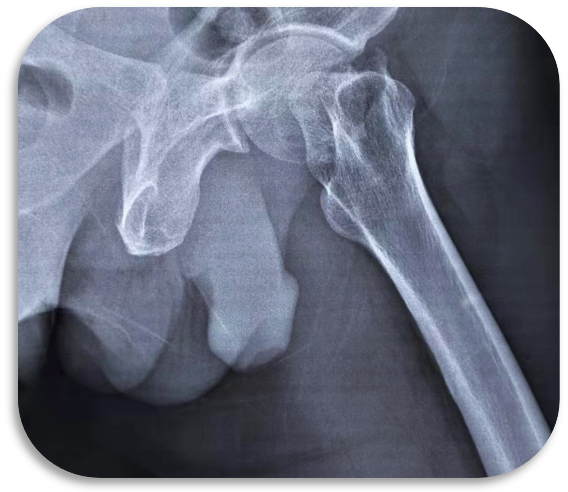

案例1 全髋关节置换术

人工股骨头置换术